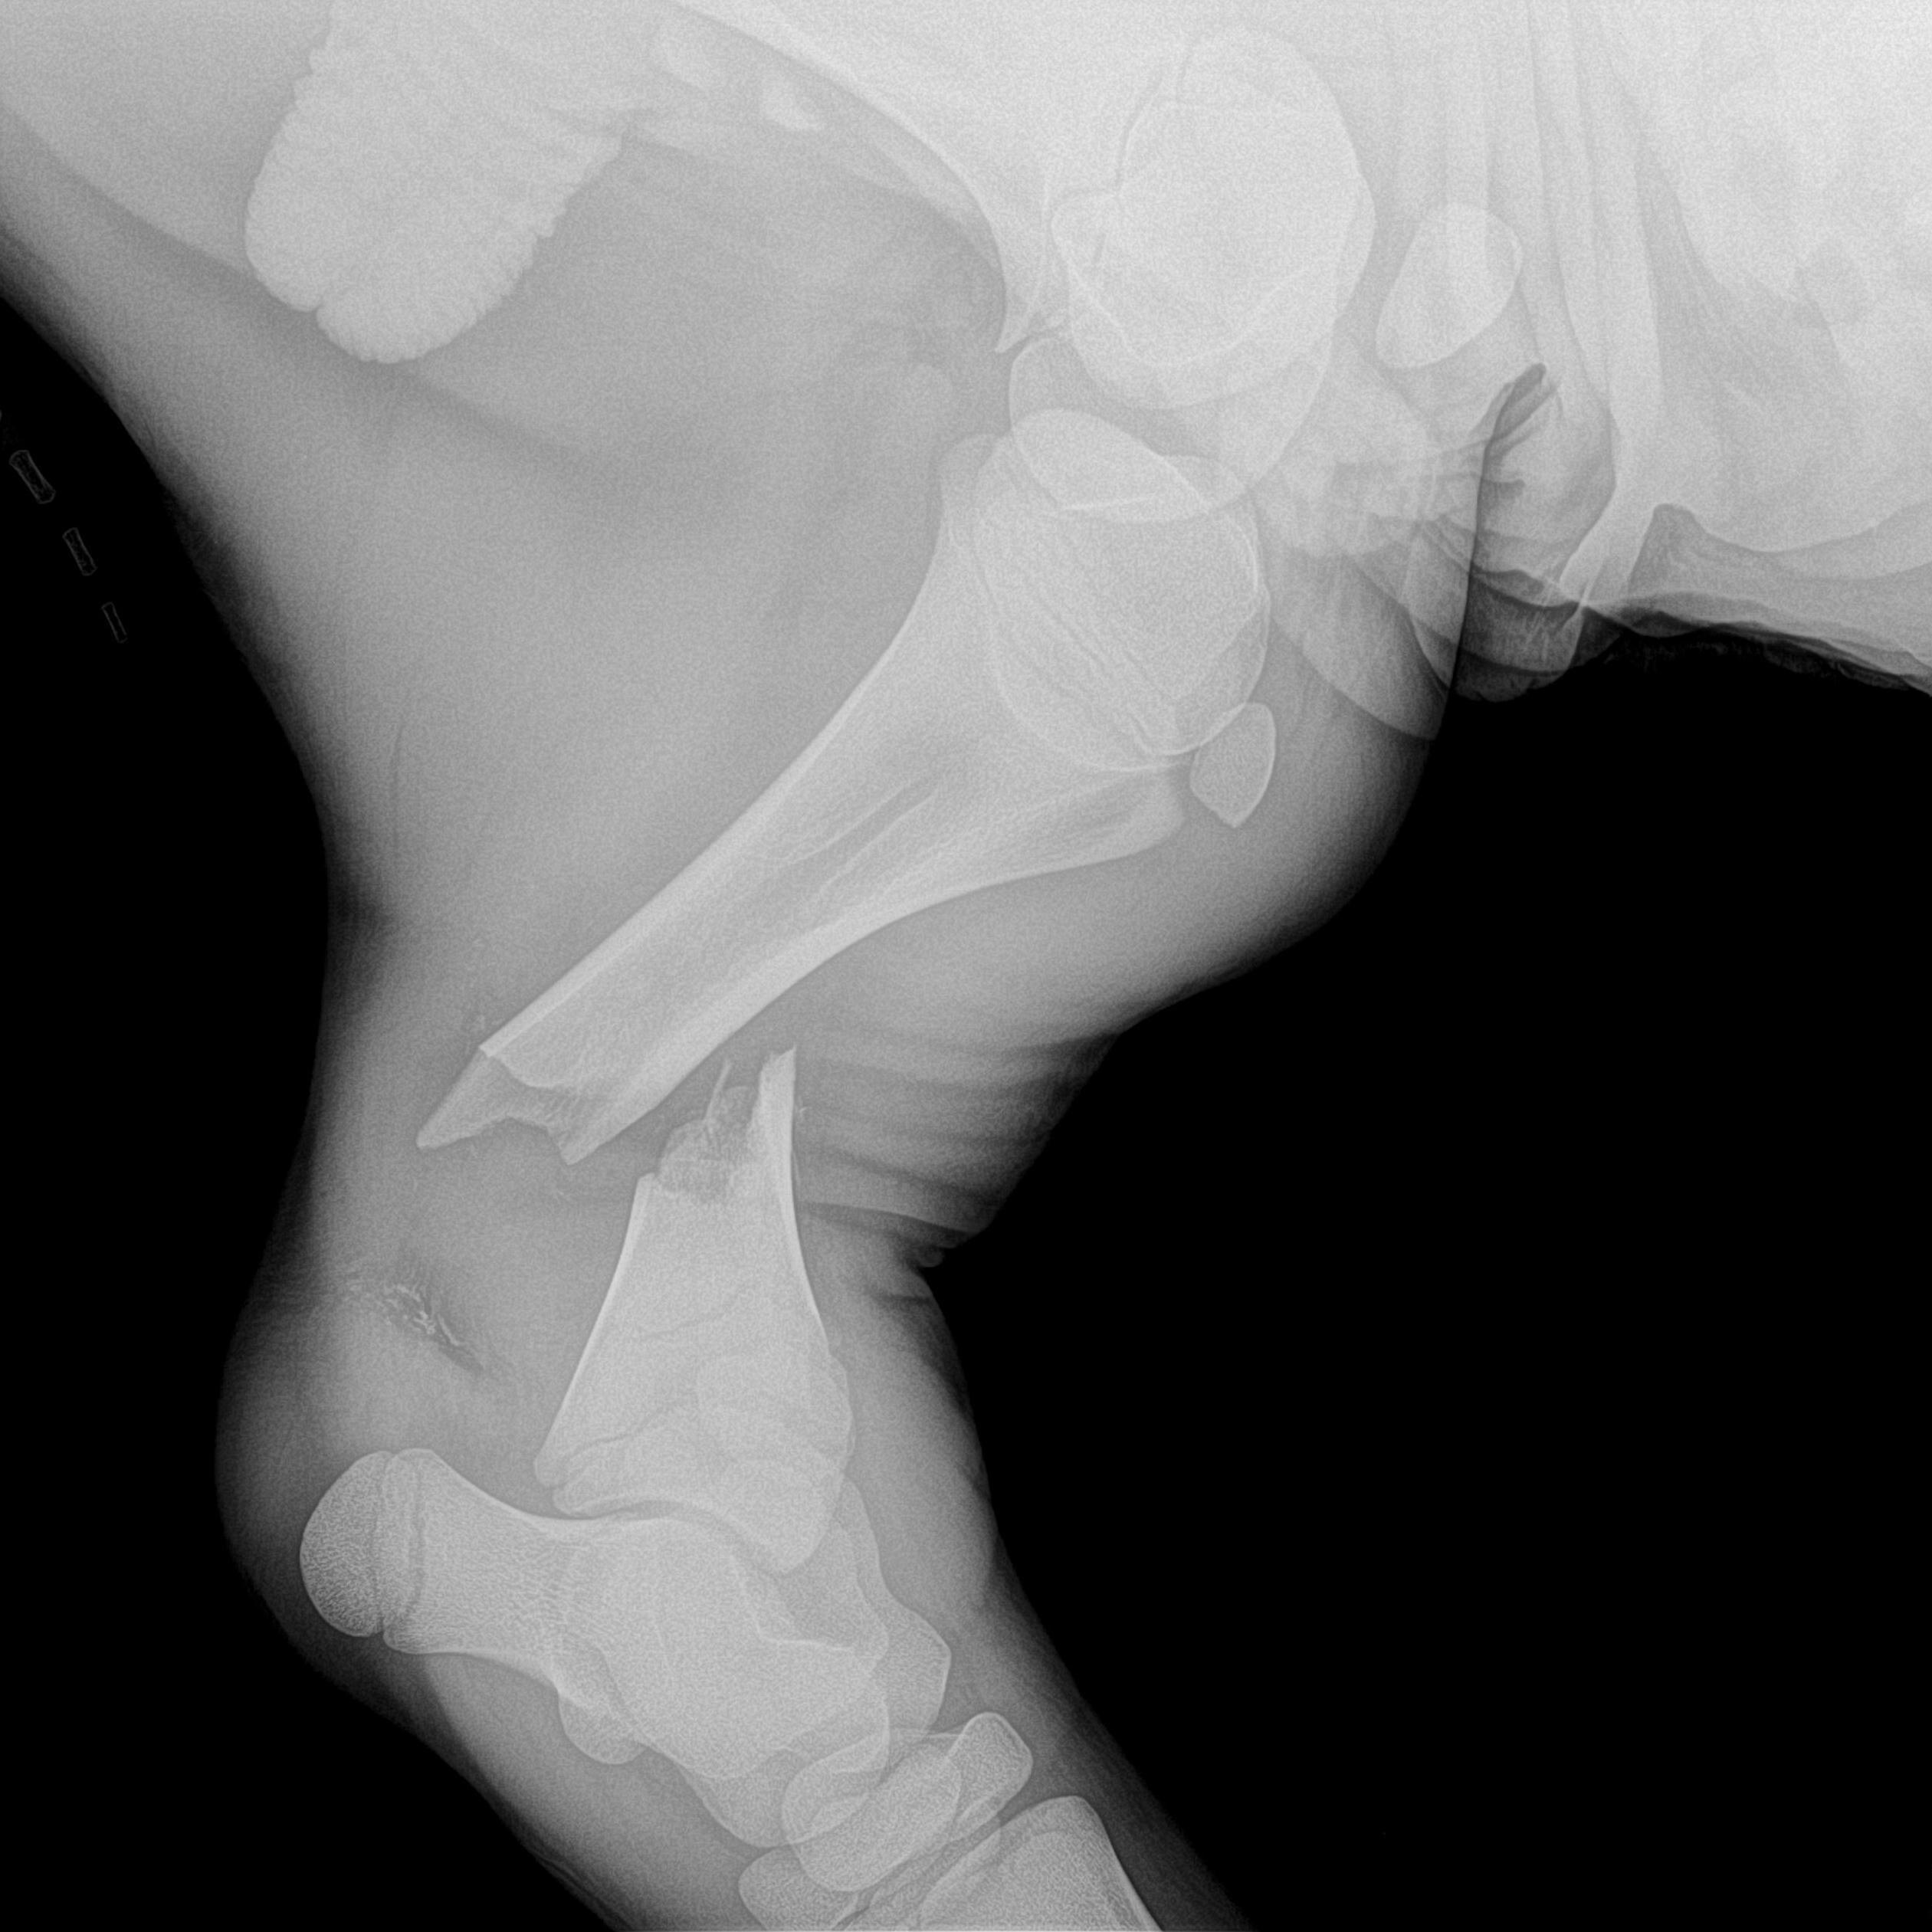

Radiographie des membres

Très utile lors de la recherche de fractures, la radiographie des membres permet également l'évaluation de différents problèmes articulaires tels que l'arthrose ou la dysplasie.

fracture d'un membre antérieur d'un chien